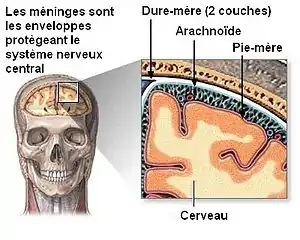

D’aspect fragile et transparent, la pie-mère est située sous la dure-mère et l’arachnoïde.

Contrairement aux feuillets plus externes (arachnoïde et dure-mère) qui suivent l’endocrâne, la pie-mère dans sa partie cranienne épouse étroitement le relief du parenchyme en suivant les sillons, scissures et circonvolutions du cortex cérébral, ce qui fait que sa surface est beaucoup plus importante que celles des autres méninges qui sont tendues au-dessus des renfoncements du tissu nerveux. Les espaces ainsi formés entre la pie-mère et l’arachnoïde sont appelés espaces sous-arachnoïdiens ; certains sont plus largement dilatés en ce qu’on appelle des citernes sous-arachnoïdiennes, elles sont situées à la base du crâne principalement autour du tronc cérébral. Les espaces sous-arachnoïdiens sont remplis de liquide cérébrospinal anciennement appelé liquide céphalo-rachidien (LCR) et traversés par des trabéculations ou travées arachnoïdiennes qui attachent la pie-mère à la face interne de la membrane arachnoïde.

- protecteur : elle est le plus interne feuillet des méninges qui protègent le cerveau et la moelle épinière.

Une coupe des différents méninges.